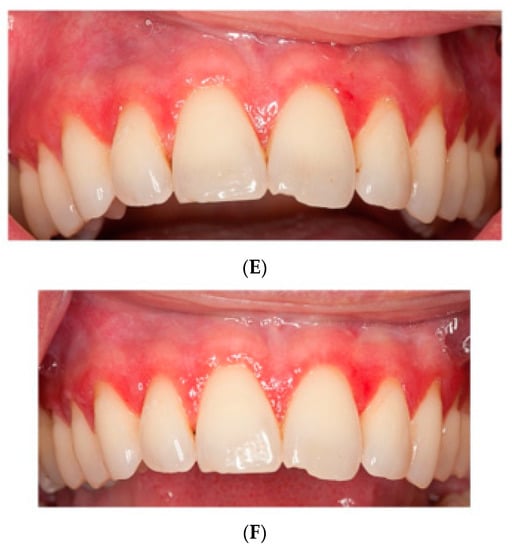

3.5. Clinical Severity Index